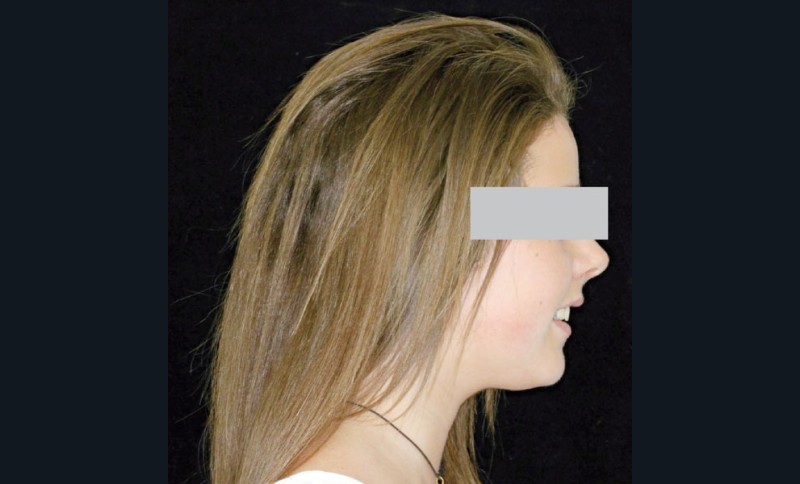

Camille âgée de 12 ans et 7 mois se présente à la consultation adressée par son chirurgien-dentiste.

Son profil convexe s’inscrit dans un contexte de rétrognathie hyperdivergente associée à une proalvéolie et un encombrement maxillo-mandibulaire.